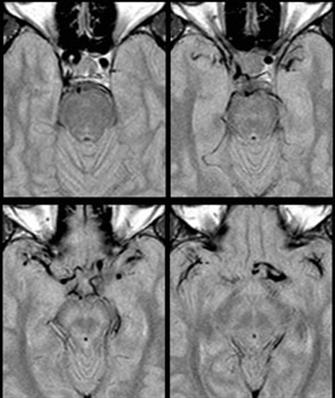

Fig. 1: Dolichoectasia of the suprasellar segment of the left internal carotid artery with compression of the optic chiasm

Internal Carotid Artery dolichoectasia is particularly interesting because the artery normally already contains one hairpin turn. Seen in an MRI as two individual arteries at this hairpin, a carotid artery dolichoectasia can progress so far as to produce a second hairpin turn and appear as three individual arteries on an MRI. In the case of a dolichoectasia of the Internal Carotid Artery (ICD), the pathogenesis is primarily related to compression of the Optic Nerves at the Optic Chiasma (see Fig. 1 and 2).